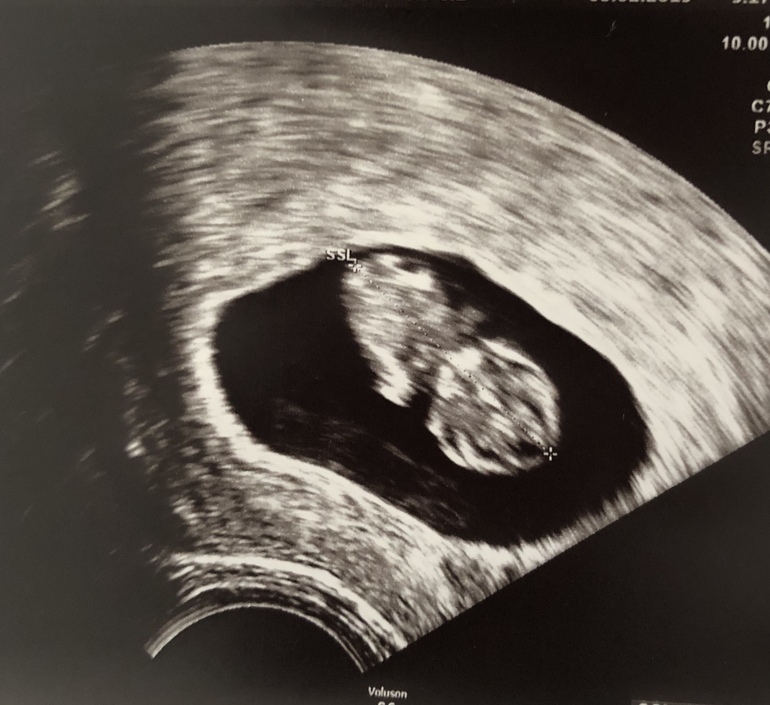

Полных 7 недель отлично видно. Вот наше фото было в 7 нед. Есть что разглядеть)

мне как после УЗИ выдали фотку, сразу своему сказала, что девочка похоже опять)

Видно на не редактированный фотке. И контуры не всегда четкие, но он определенно выделяется. Ну и к вопросу нормально это или нет - моя третья дочь со мной)))) Так что нормально)))